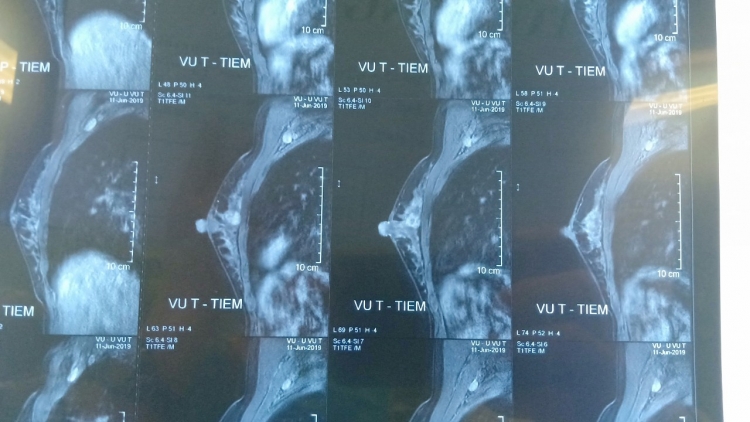

Sau đó bệnh nhân được đưa đi khám tại một bệnh viện ở Hà Nội. Bệnh nhân được chụp cộng hưởng từ (MRI) sọ não và phát hiện thấy một khối u có kích thước lớn khoảng 3cm ở tiểu não.

Tại đây các bác sỹ chẩn đoán sơ bộ là ung thư di căn não chưa rõ tổn thương nguyên phát. Do bệnh nhân đang có thai nên không thể chụp X quang, cắt lớp vi tính và chẩn đoán bằng Y học hạt nhân để xác định nguyên nhân vì có thể ảnh hưởng tới thai nhi.

Bệnh nhân có thể khám bằng tay, chụp nhũ ảnh, chụp MRI. Trường hợp lo sợ chụp sẽ ảnh hưởng tới thai nhi, các bác sĩ hoàn toàn có thể sử dụng áo chì để bảo vệ các thai nhi trong bụng.